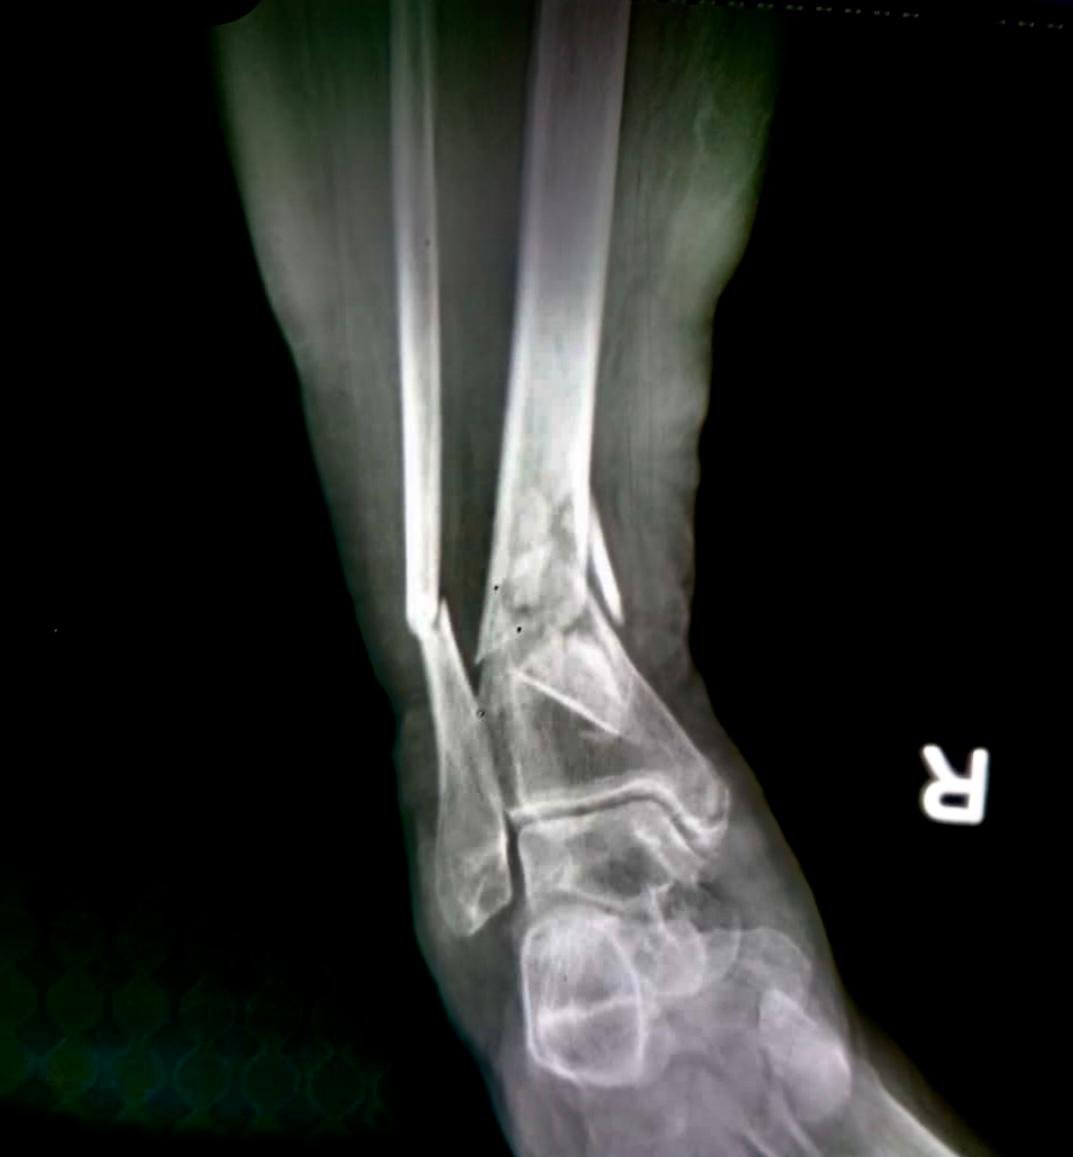

Pre op & postop X-ray compound fracture lower tibia

& fibula | Heal fracture pre & postop | Clavicle